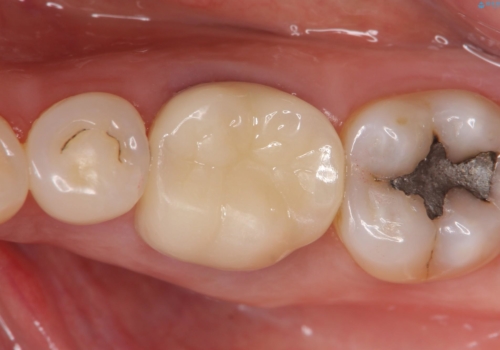

再根管治療終了後、オールセラミッククラウンにて補綴を行いました。

今回用いたオールセラミッククラウンはジルコニアフレームという白い素材の上にセラミックを盛っているため、審美性が非常に高いのが特徴です。

また、ジルコニアは人工ダイヤモンドの材料にも使われているほど高い強度を持っており、そのためオールセラミッククラウンは審美性だけでなく、奥歯やブリッジの補綴も可能とするクラウンです。